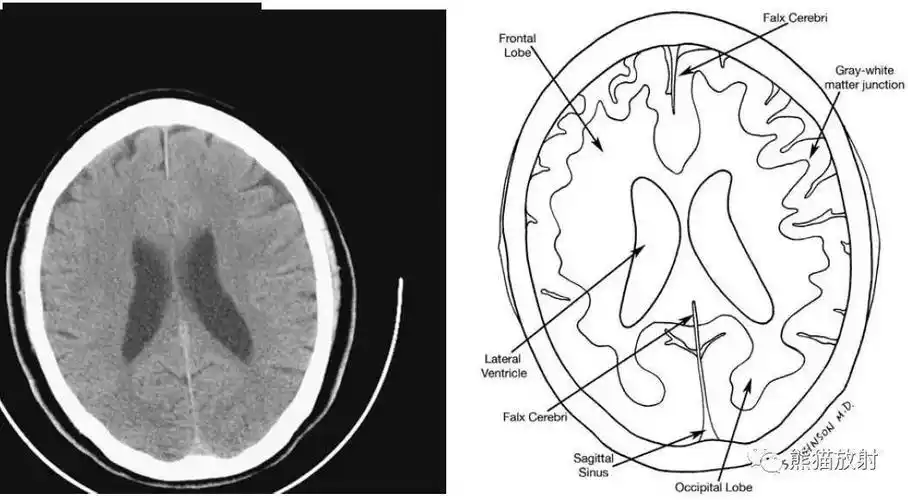

颅脑ct的正常解剖

详细标注版——颅脑ct正常解剖图谱_中央_小脑_纤维